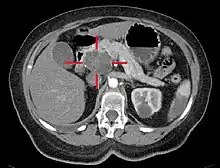

Axial CT image with IV contrast and added color: Cross lines towards top left surround a macrocystic adenocarcinoma of the pancreatic head.

Medical imaging techniques, such as computed tomography (CT scan) and endoscopic ultrasound (EUS) are used both to confirm the diagnosis and to help decide whether the tumor can be surgically removed (its "resectability").[12] On contrast CT scan, pancreatic cancer typically shows a gradually increasing radiocontrast uptake, rather than a fast washout as seen in a normal pancreas or a delayed washout as seen in chronic pancreatitis.[56] Magnetic resonance imaging and positron emission tomography may also be used,[2] and magnetic resonance cholangiopancreatography may be useful in some cases.[32] Abdominal ultrasound is less sensitive and will miss small tumors, but can identify cancers that have spread to the liver and build-up of fluid in the peritoneal cavity (ascites).[12] It may be used for a quick and cheap first examination before other techniques.[57]